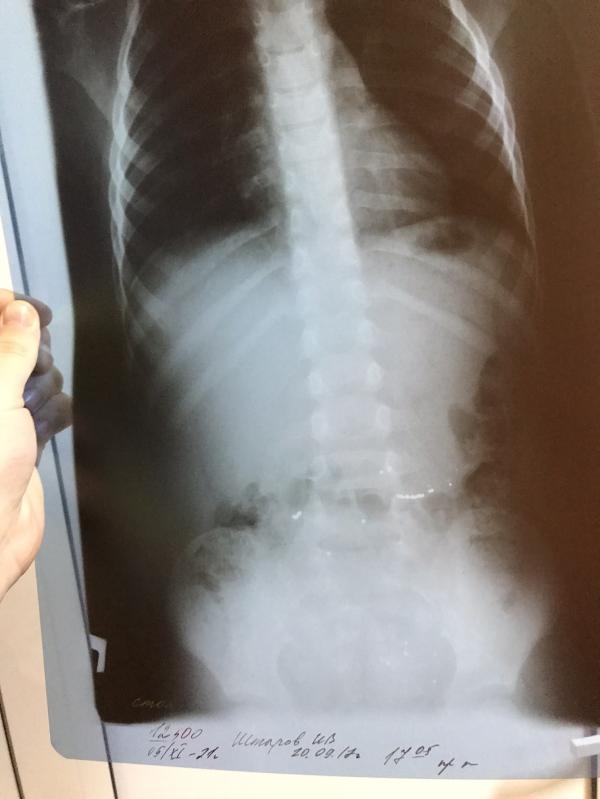

Я говорю сделайте рентген чтоб перестраховаться , ну конечно не мало он съел отправили домой , сказали все выйдет .

Стекло он не съел , вот на снимках ртуть видна , то есть кончик только , но и собрала я не мало ртути